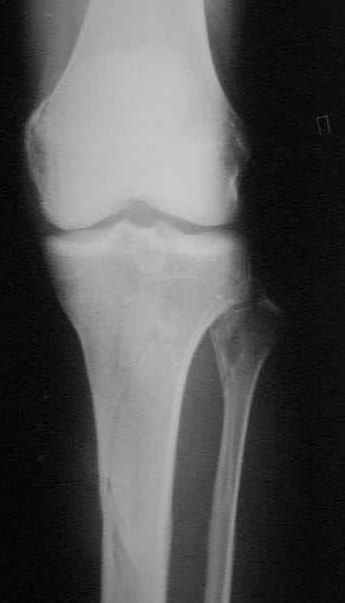

Здравствуйте коллеги! 10.07.2006 года поступил молодой человек 26 лет с Диагнозом:

Открытый (2 В Каплан) многооскольчатый перелом левого бедра. Перелом межмыщелкового возвышения большеберцовой кости без смещения слева. Открытый (1 А Каплан) перелом с/3 -н/3 костей правой голени, перелом пяточной кости справа. На седьмые сутки выполнены операции:1. ЗИМО (статически, Chm-CHARFIX) левого бедра. 2. Остеосинтез стержневым аппаратом костей правой голени и пяточной кости. См. r-gr. На сегодня аппарат демонтирован, больной ходит с ограниченной нагрузкой. Смущает стояние отломков в верхней трети бедра (как то не задумались при планировании операции о реконструктивном или гамме штифте ) хватит ли этих двух винтов для стабильности? С Уважением Владимир Бахарев.